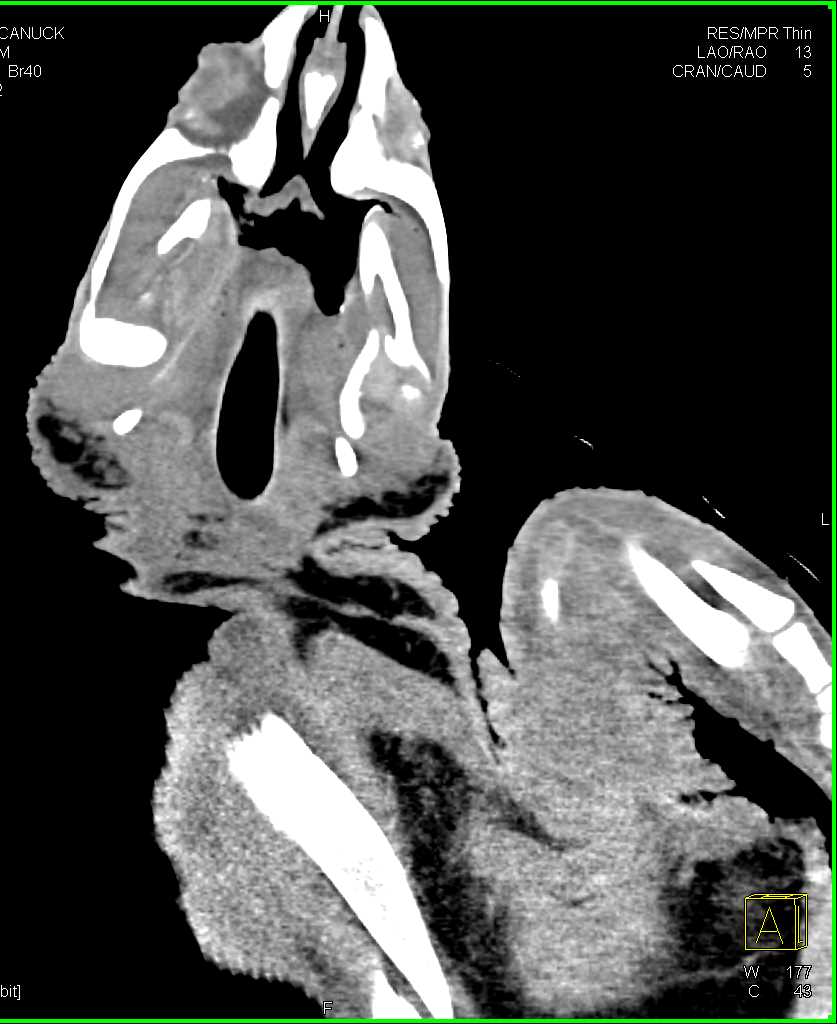

Turtle Lungs with Bronchial Tree